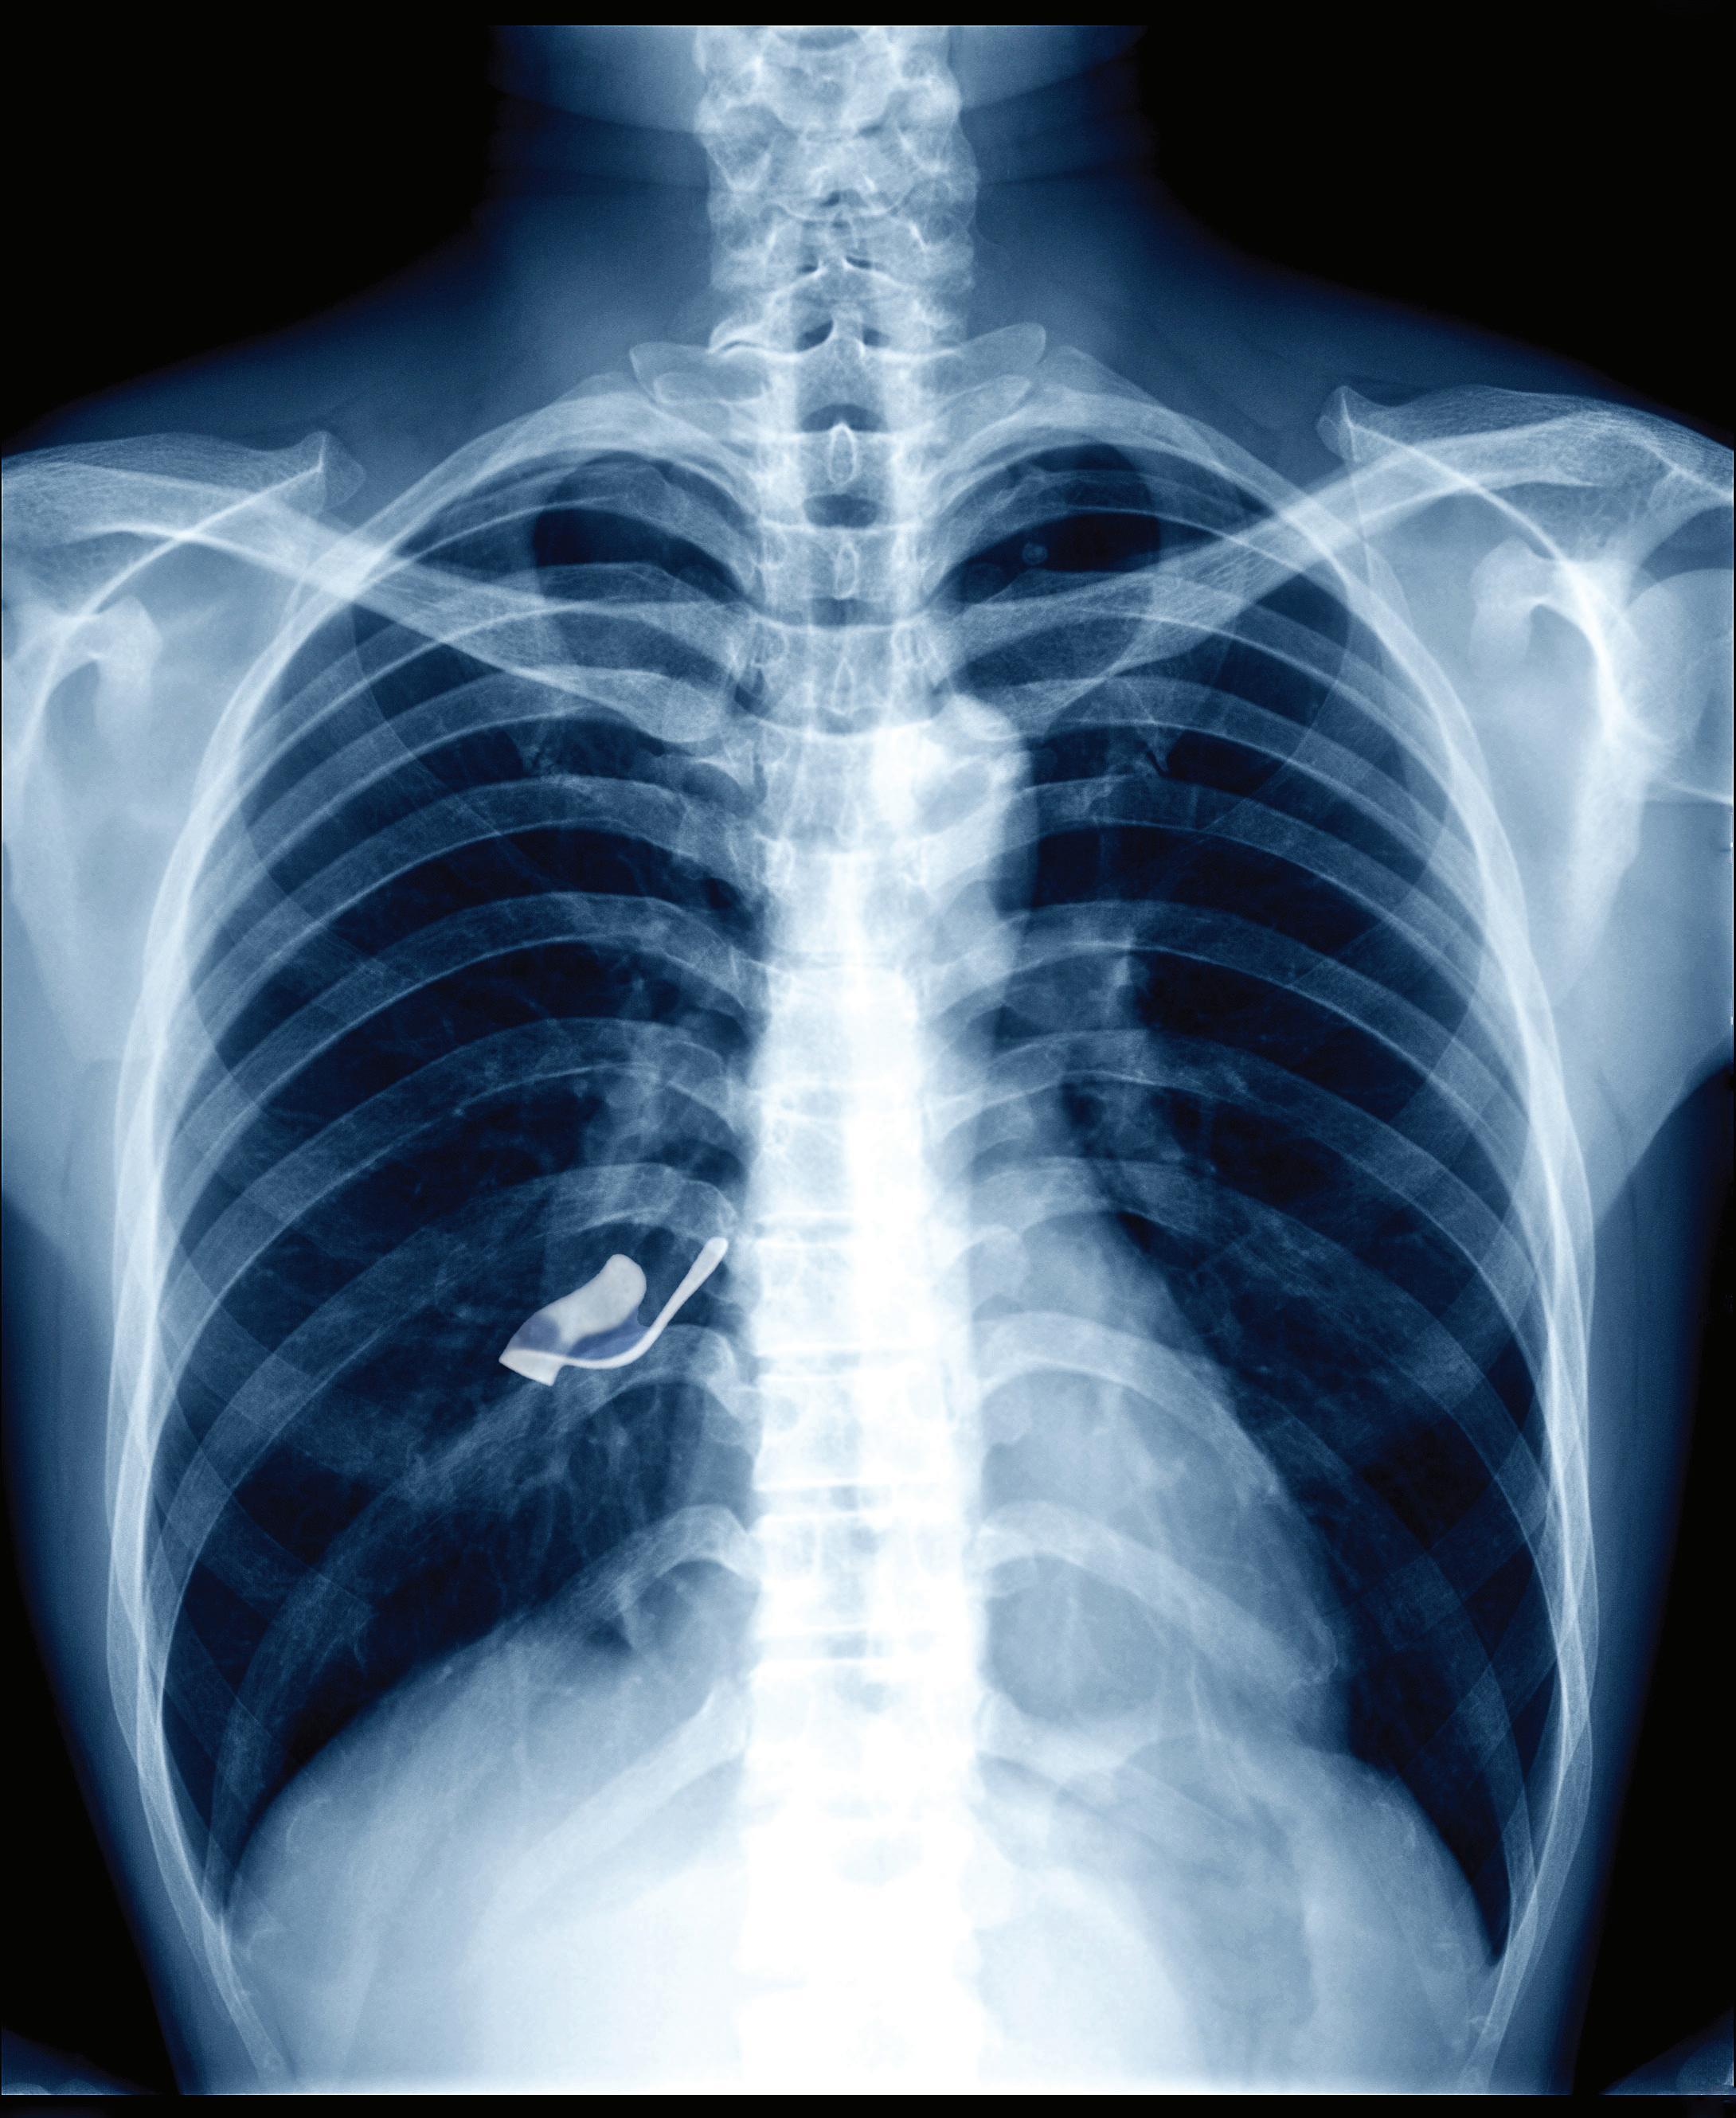

11 days after appendectomy, tests for acute abdominal pain revealed a

left inside the patient.

Surgical miscounts are considered never events because they are usually preventable by following established procedures.

ProAssurance offers risk assessments designed to help practices minimize errors by establishing and evaluating safety procedures and communication protocols.

With reliable procedures in place, our insureds are more likely to reduce errors in their medical practice, avoid claims, and make claims more defensible if they do occur.